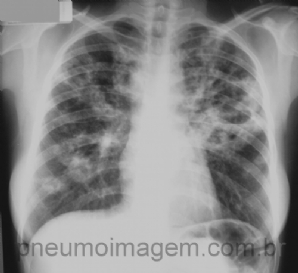

CASO CLÍNICO #31

Qual o nome desse sinal e o mais provável diagnóstico a ele relacionado? Deixe os seus comentários abaixo. ***** What is the name of the sign and the most likely diagnosis related to it? Give your comments below.